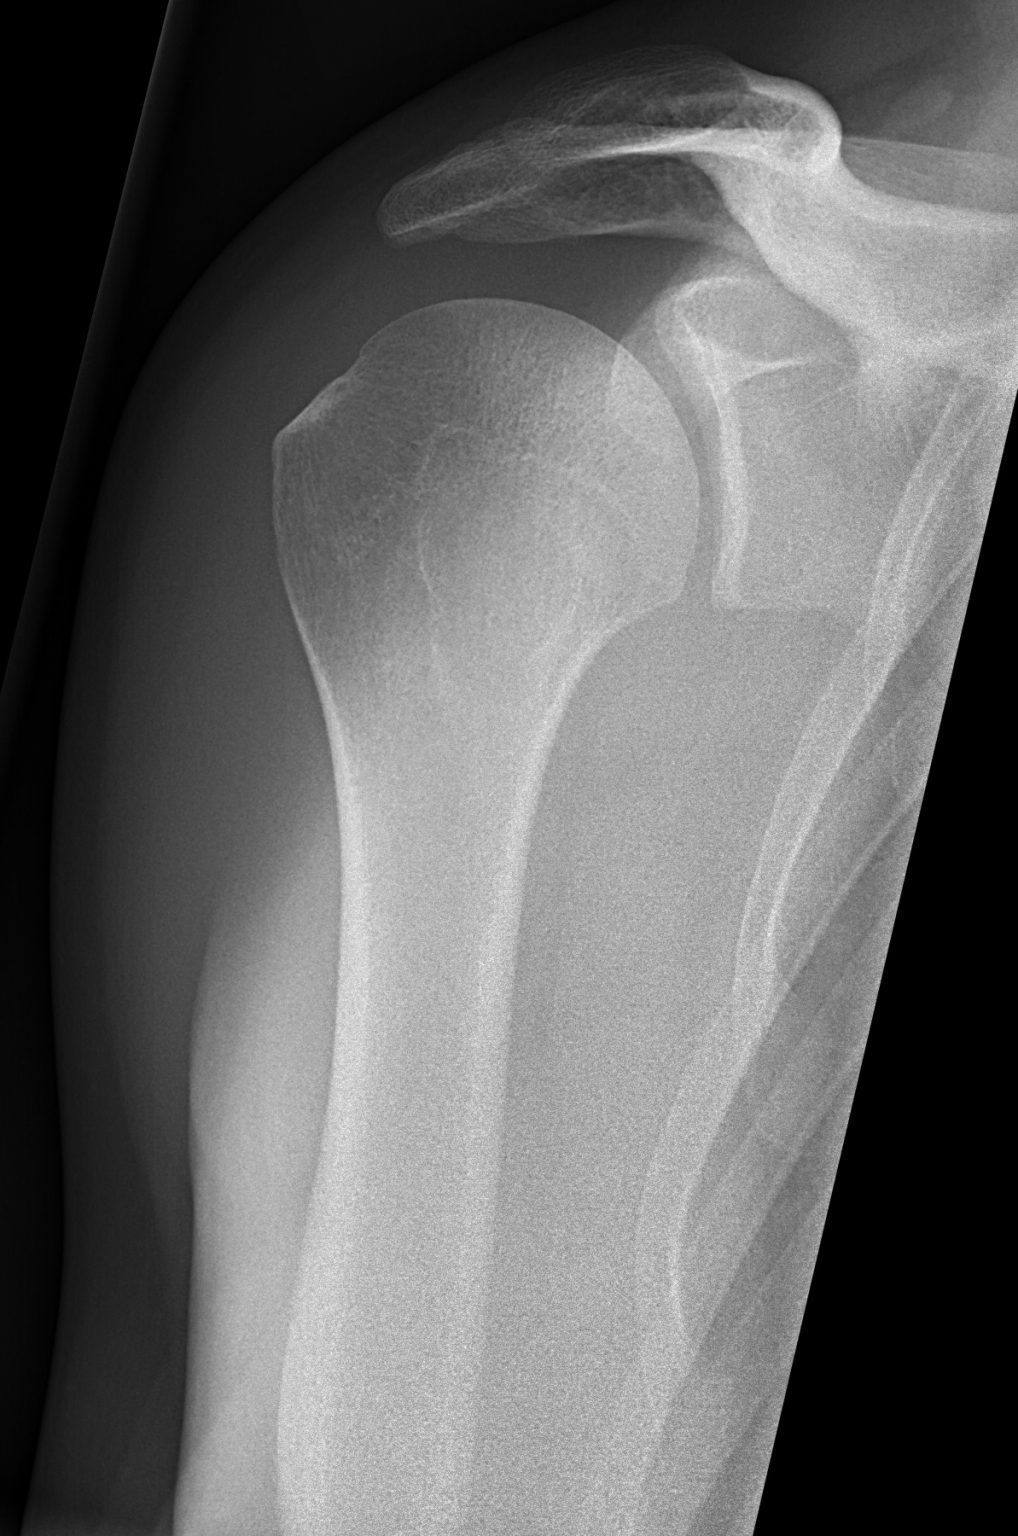

Grashey X Ray Labeled . The projection is used to assess the. the shoulder ap glenoid view also known as a true ap or a 'grashey view ' is an additional projection to the two view shoulder series. The overlap between the humerus and the glenoid seen on the ap view is removed in the grashey projection by rotating the patient posteriorly or angling the beam laterally. Mri is best for evaluating soft tissue structures and evaluating bone contusions or trabelcular. glenohumeral “true” ap (grashey) view. The true ap view, or grashey view ( fig. the shoulder series is fundamentally composed of two orthogonal views of the glenohumeral joint including the. The body has to be rotated about 30 to 45 degrees towards the shoulder to be imaged, and the standing or sitting patient.

The true ap view, or grashey view ( fig. Mri is best for evaluating soft tissue structures and evaluating bone contusions or trabelcular. glenohumeral “true” ap (grashey) view. The body has to be rotated about 30 to 45 degrees towards the shoulder to be imaged, and the standing or sitting patient. the shoulder series is fundamentally composed of two orthogonal views of the glenohumeral joint including the. The projection is used to assess the. The overlap between the humerus and the glenoid seen on the ap view is removed in the grashey projection by rotating the patient posteriorly or angling the beam laterally. the shoulder ap glenoid view also known as a true ap or a 'grashey view ' is an additional projection to the two view shoulder series.